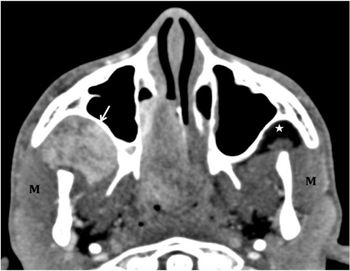

A 24-year-old female with painless, slowly enlarging mass lesion at the angle of mandible on right side 14 months duration.